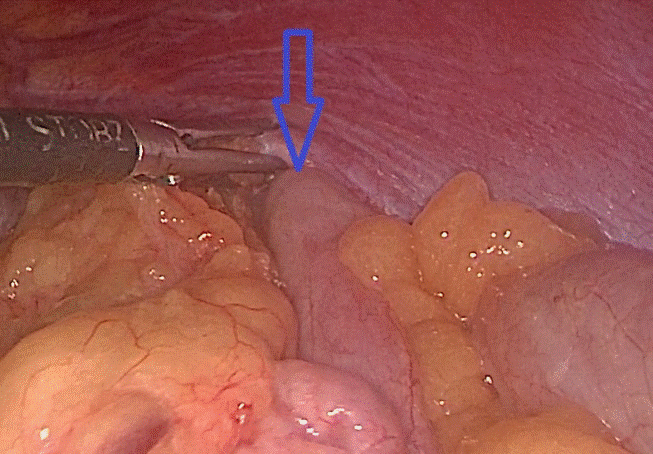

Đại tràng chui qua lỗ thoát vị lên trên ngực tráiĐại tràng chui qua lỗ thoát vị lên trên ngực trái

Khi mổ nội soi, phẫu thuật viên nhận thấy gần toàn bộ đại tràng ngang, lách, dạ dày và mạc nối lớn đã chui qua cơ hoành lên khoang màng phổi bên trái. Sau khi đưa các tạng trên trở lại ổ bụng, tổn thương cơ hoành bên trái lộ rõ là một lỗ khuyết rộng khoảng 6x8cm.

Đây chính là nguyên nhân gây ra thoát vị, kết hợp với tiền sử có chấn thương, chẩn đoán trong mổ là thoát vị hoành trái do vỡ cơ hoành. Cơ hoành vỡ đã được các phẫu thuật viên khâu phục hồi kín, ca mổ diễn ra trong 1 giờ 30 phút.